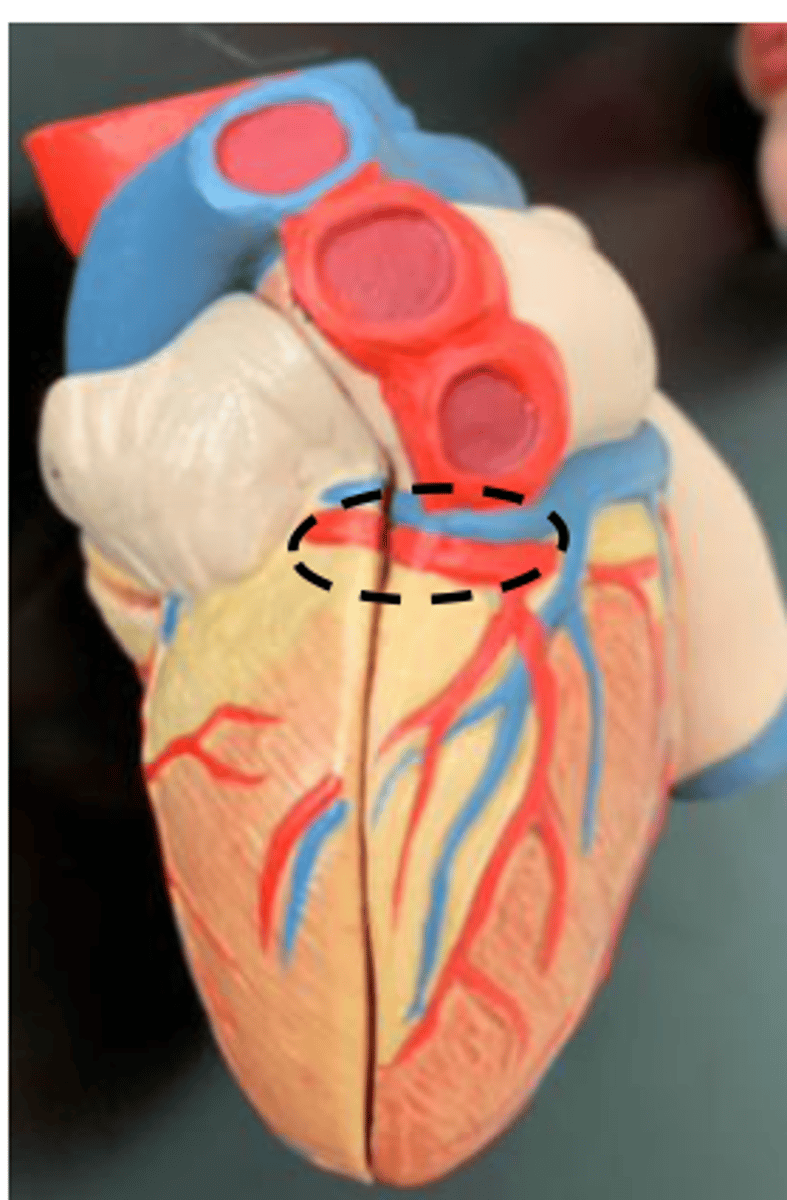

coronary sulcus

AKA (atrioventricular sulcus)

<p>AKA (atrioventricular sulcus)</p>